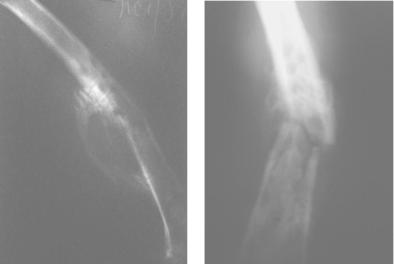

Основную роль в диагностике хронического остеомие-

лита играет рентгенографическое исследование кости, кото-

рое позволяет обнаружить характерные для остеомиелита изменения в костной ткани: утолщение надкостницы («ассимилированный периостит»); выраженный остеосклероз, окаймляющий остеомиелитические полости и соответствующий секвестральной коробке (рис. 57); наличие в секвестральной коробке тени секвестра. Выполненная фистулогра-

Рис. 57. Рентгенограммы при хроническом остеомиелите

бедренной кости

фия позволяет исследовать расположение, направление и форму свищевых ходов и их связь с очагом поражения кости.